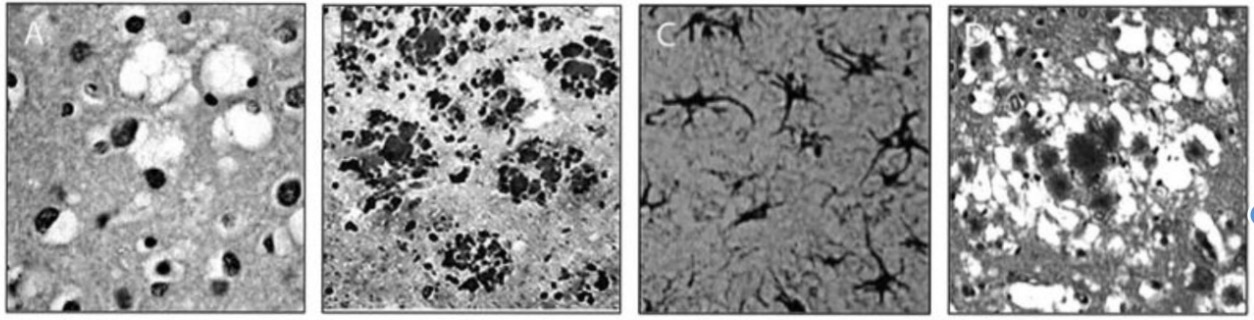

Tissue pathology

Vacuoles – The typical damage that occurs in the disease

◦ Hence – “spongiform”

The void regions form from cells that have died, having left an empty region in its place

Tissues in prions diseases

Spongiform degeneration

Prp plaques (formed by over accumulation of protein structures)

Gliosis

Florid Plaque